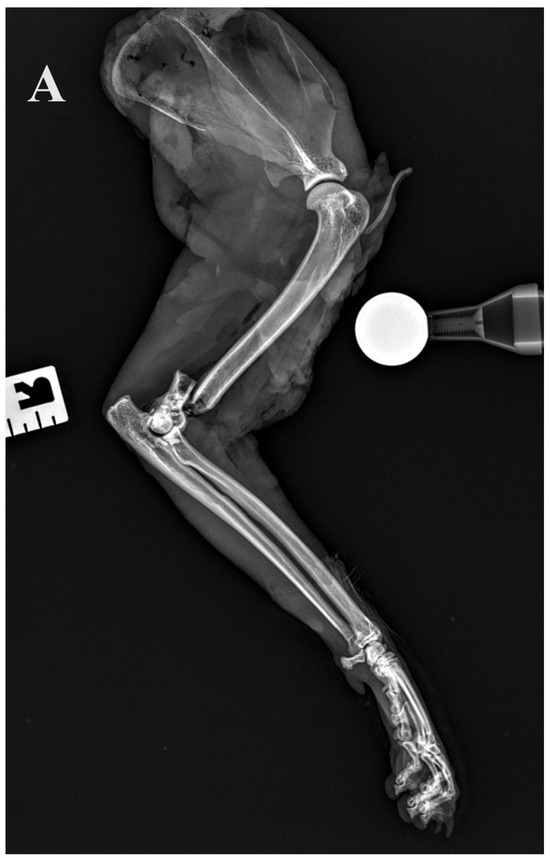

Figure 5.

(A,B) Initial lateral and cranio–caudal radiographs of the right forelimb of a female domestic cat show a displaced Y-T fracture. (C,D) Postoperative lateral and cranio–caudal radiographs show a small articular surface defect (<1 mm) of humeral condyle and adequate alignment, adjacency and apparatus (2.0/2.4/2.7 3D printed plate, 2.4/2.7 straight interlocking bone plate and screws).